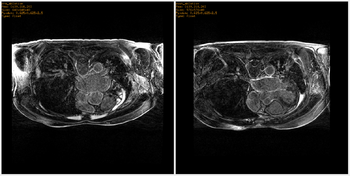

Left) Pre ablation. Right) Post ablation.

Post registered to pre using Slicer pipeline affine registration.